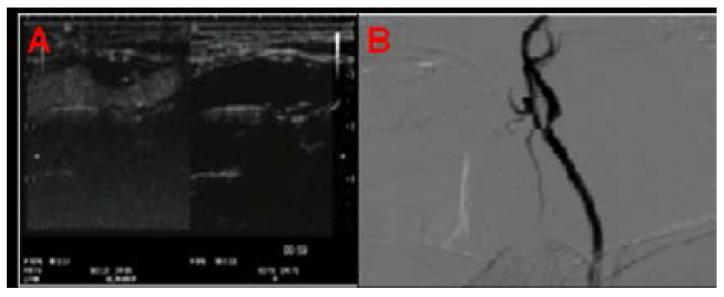

Thirty-six successive patients (11 women and 25 men, mean age: 65.0 ± 9.2, range: 43-78 years) with internal carotid artery (ICA) stenosis were tested by CEUS and DSA. These tests were carried out by means of Hitachi Preirus ultrasound machine for CEUS and Allura Xper FD20 system (Philips Medical Systems, Nederland B.V.) for DSA. 1.2 ml SonoVue (Bracco, Switzerland) was used a s contrast agent.

The results clearly indicated that there were no noteworthy variations among the distributions recorded by CEUS as well as DSA for the four tested groups. The percentage of diameter stenosis calculated by CEUS was clearly in accordance with the DSA images. CEUS showed accurate results with good specificity and sensitivity at 50%, 70%, and 100%. Also, CEUS performance was relatively better than DSA in the diagnosis of ICA and suitability of CEA.

对 36 例 ICA 狭窄患者(11 名女性和 25 名男性,平均年龄:65.0±9.2 岁,范围:43-78 岁)分别进行了 CEUS 和 DSA 检查。CEUS 检查使用日立 Preirus 超声机,DSA 检查使用 Allura Xper FD20 系统(荷兰皇家飞利浦电子公司)。采用 1.2ml SonoVue(Bracco,瑞士)作为造影剂。

结果表明,CEUS 和 DSA 对四组狭窄程度的测量值分布无明显差异。CEUS 计算的直径狭窄百分比与 DSA 图像一致。CEUS 在诊断 ICA 狭窄和 CEA 适用性方面具有 50%、70%和 100%的良好特异性和敏感性。CEUS 在诊断 ICA 狭窄和 CEA 适用性方面的性能也优于 DSA。